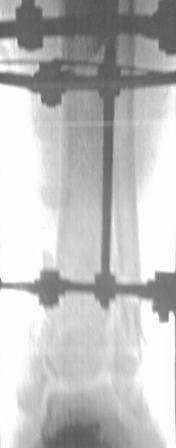

Открытый перелом 43.С3.3

Больной 41г переведен из ЦРБ, травма в результате ДТП- 5 дней назад, произведена ПХО раны, наложена гипсовая повязка.

Об-но; начиная с с/з голени продольно - почти циркулярная рана, с признаками инфицирования - покраснение, отечность, усиление боли, местная т-ра и мутные кровянистые выделения из раны, и выраженная деформация голени. В отд нашей коллегой в экстренном порядке в задней поверхности голени щвы распушены, выпушено около 50мл мутной гематомы, АВФ, умеренная дистракция, антибиотики, и т.д.

Наш план; после устранения воспалительных процессов, перемонтаж аппарата, репозиция оставшихся смещений спицами с упорной плошадкой и стабилизация аппарата, дальше по обстановке.